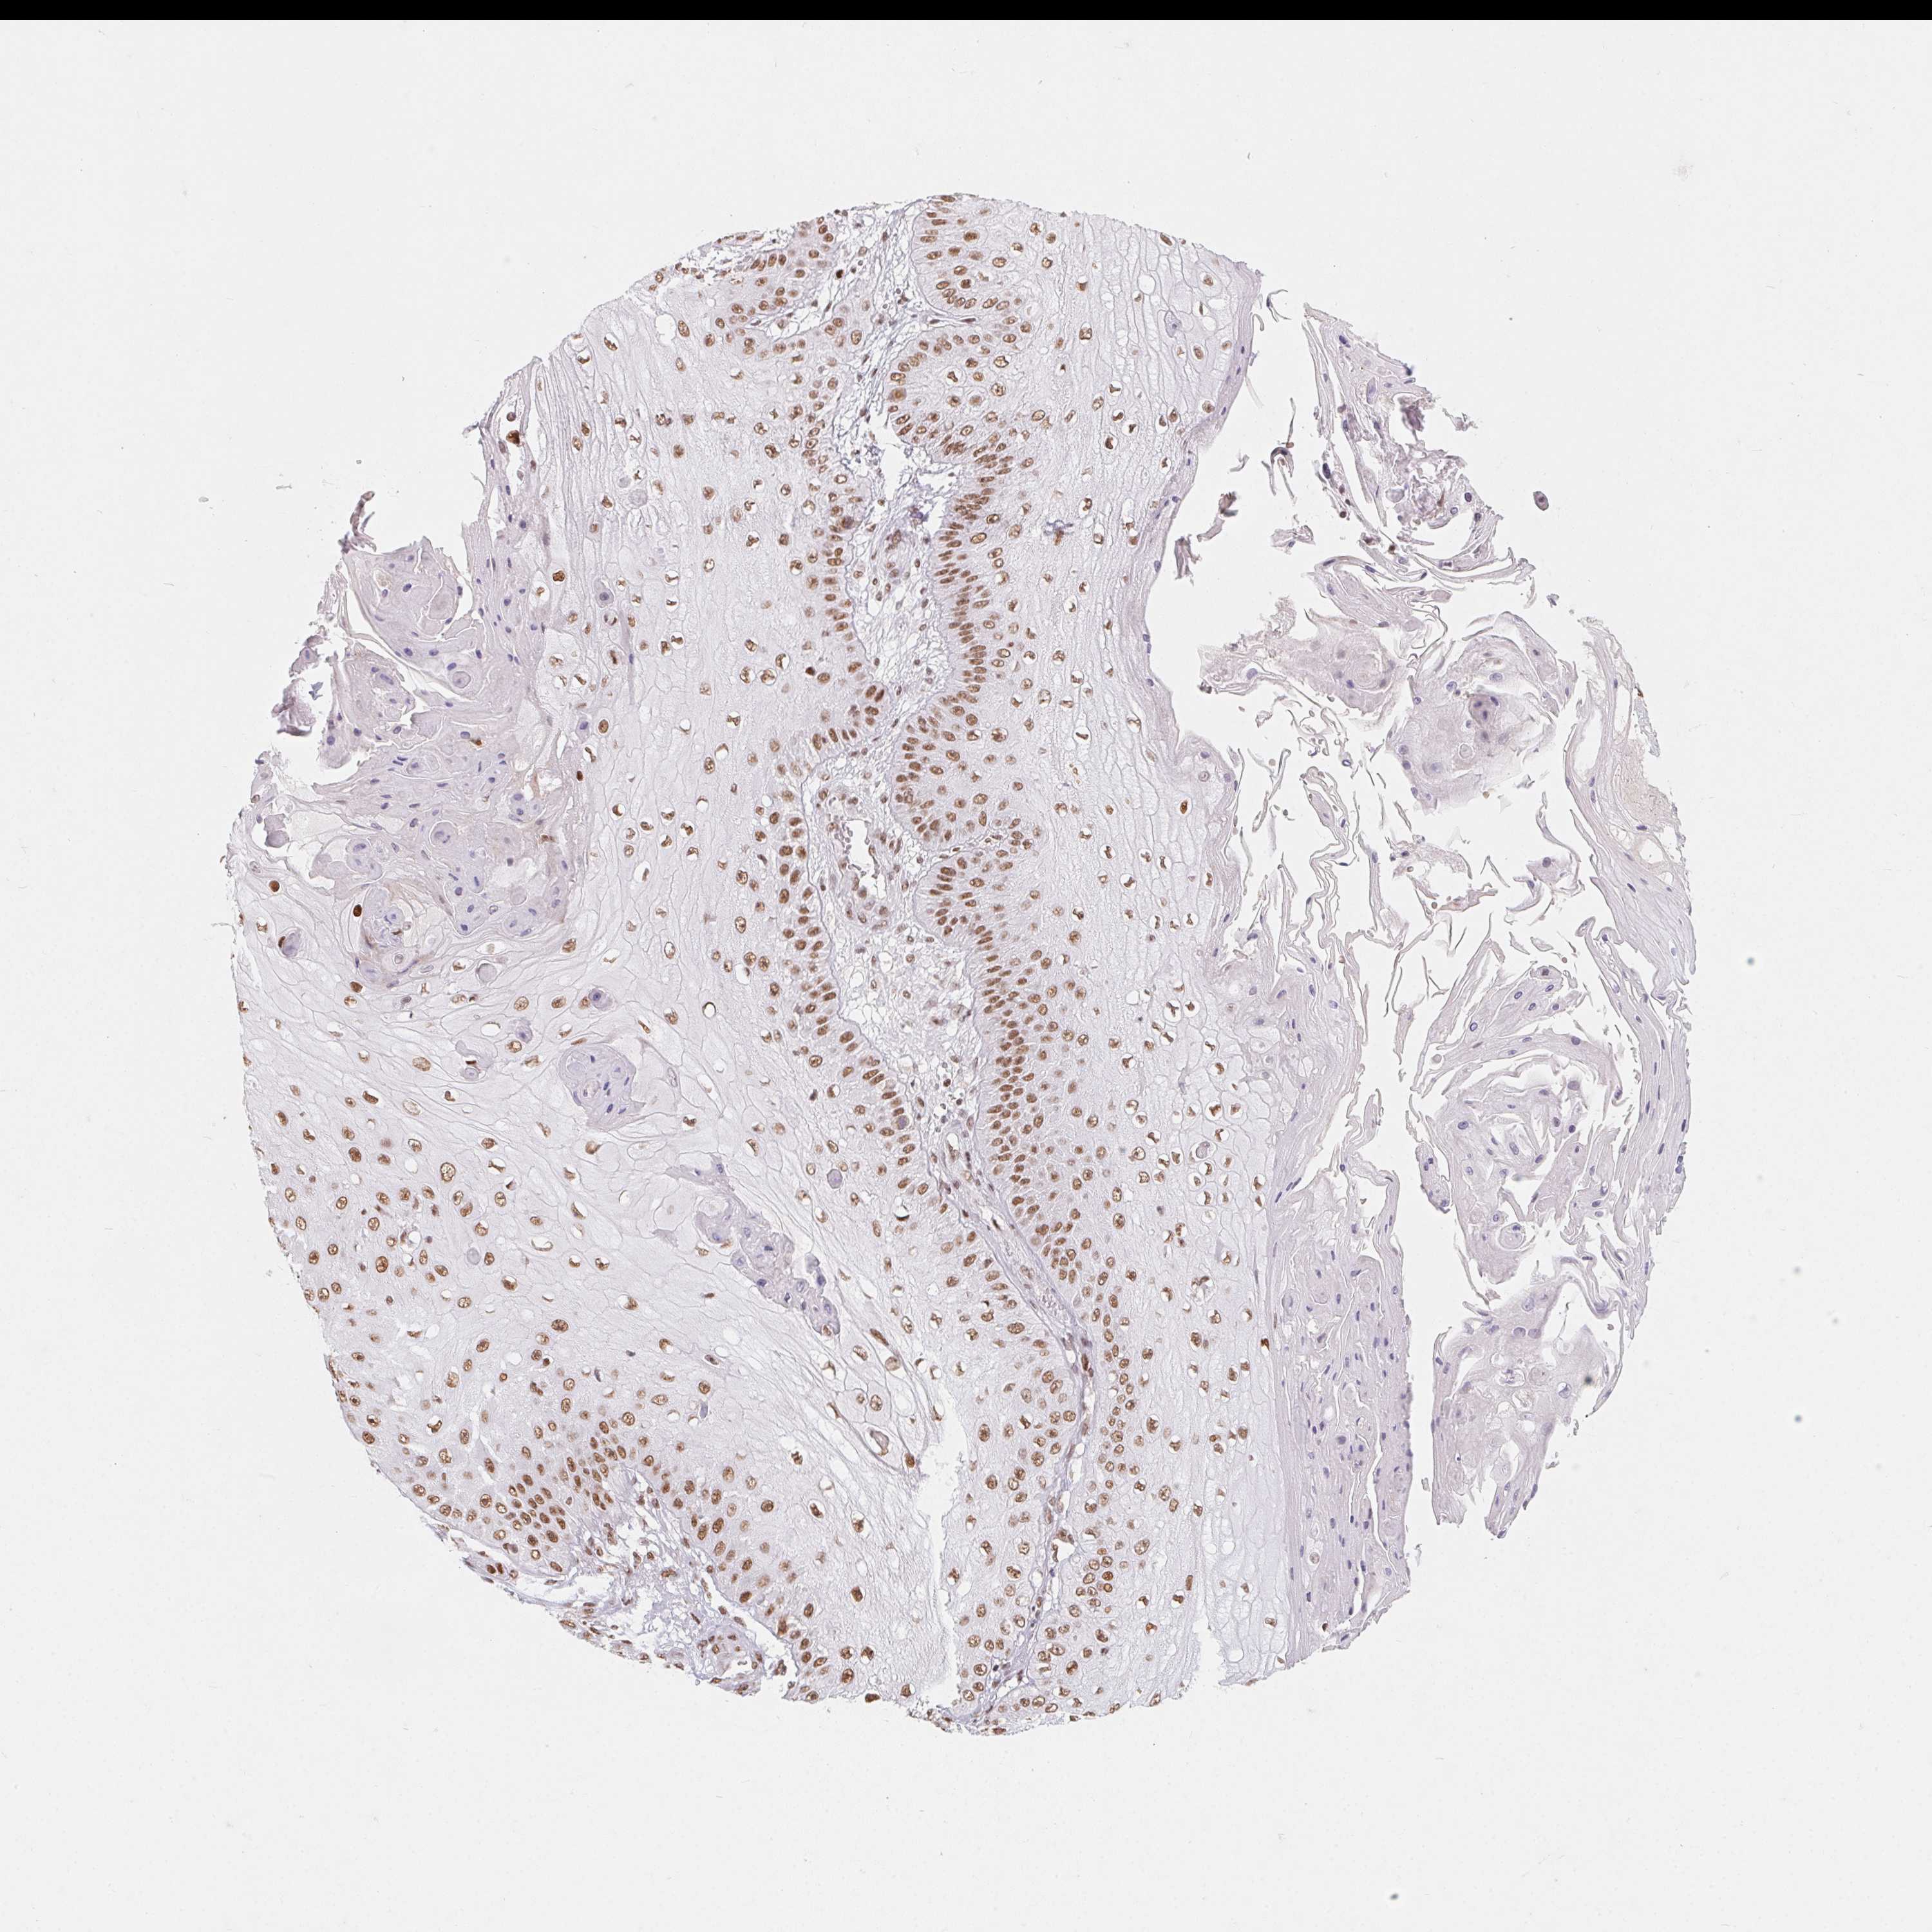

CANCER SKIN CANCER Show tissue menu

Basal cell and squamous cell cancer

SKIN CANCER - Protein expressioni

A mouse-over function shows sample information and annotation data. Click on an image to view it in a full screen mode. Samples can be filtered based on level of antibody staining by selecting one or several of the following categories: high, medium, low and not detected. The assay and annotation is described here.

Antibody stainingi

Antibody staining in the annotated cell types in the current human tissue is reported as not detected, low, medium, or high, based on conventional immunohistochemistry profiling in selected tissues. This score is based on the combination of the staining intensity and fraction of stained cells.

Each image is clickable and will lead to virtual microscopy that enables deeper exploration of all samples and also displays staining intensity scores, fraction scores and subcellular localization as well as patient and tissue information for each sample.

Antibody HPA064887

Staining

High

Medium

Low

Not detected

Intensity

Strong

Moderate

Weak

Negative

Quantity

>75%

75%-25%

<25%

None

Location

Nuclear

Cytoplasmic/membranous

Cytoplasmic/membranous,nuclear

Basal cell carcinoma

BCC, high aggressive

Squamous cell carcinoma, NOS